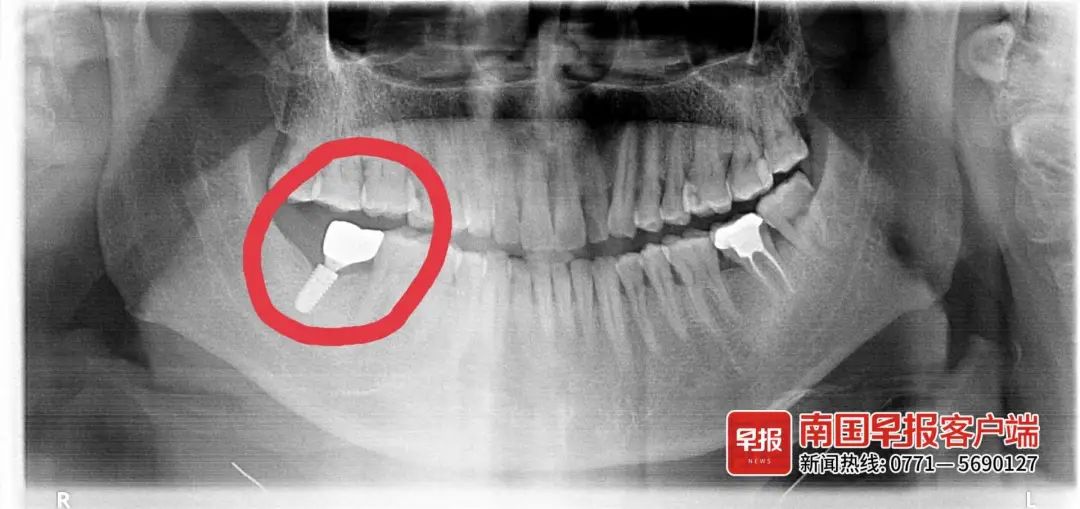

潘先生此前种植的牙齿。受访者供图

2021年6月,潘先生感觉种植的牙齿有些松动,于是到该院复查。医生检查后称,是种植牙齿的螺丝松了,需要拧紧。在医生修复牙齿时,所种的牙齿牙冠断裂了,只剩螺丝残留在牙床内。潘先生说:“医生当时说帮我弄出来,但弄了半天也无法取出。”

潘先生此前种植的牙齿牙冠断裂,只剩螺丝(图中白色部分)残留在牙床中。受访者供图